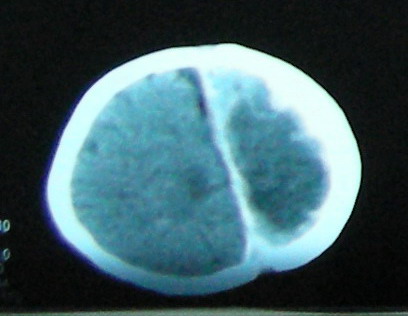

考虑:1、左额颞顶慢性硬膜下血肿(可能为产伤所致);

2、蛛网膜下腔出血;

3、左侧大脑半球及右额叶脑肿胀、梗塞(缺血性脑梗塞为脑疝所致)。

病人预后会很差。

左额颞顶慢性硬膜下血肿(可能为产伤所致);蛛网膜下腔出血,已明确,至于左侧大脑半球大片低密度影并脑组织肿胀,考虑:梗塞导致缺血缺氧性改变.至于梗塞原因随诊观察吧!

1、左额颞顶慢性硬膜下血肿;